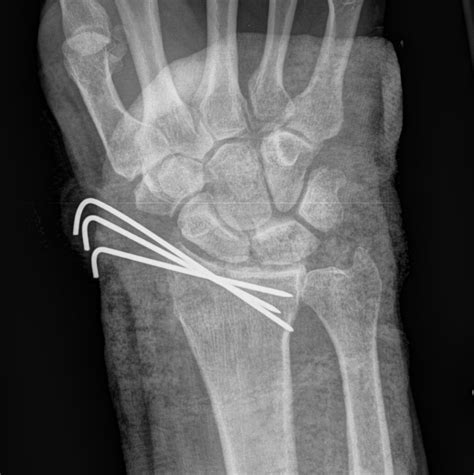

Surgical Treatment

In cases of severe fractures or when non-surgical treatment is not effective, surgery may be required. Surgical options include:

• Open Reduction and Internal Fixation (ORIF): This procedure involves realigning the bone fragments and securing them with plates, screws, or wires.

• Arthroscopy: In some cases, arthroscopic surgery may be used to repair the fracture and assess any associated ligament damage.